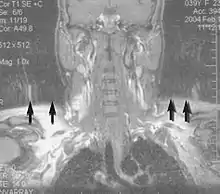

Magnetic resonance angiography (MRA) generates pictures of the arteries to evaluate them for stenosis (abnormal narrowing) or aneurysms (vessel wall dilatations, at risk of rupture). MRA is often used to evaluate the arteries of the neck and brain, the thoracic and abdominal aorta, the renal arteries, and the legs (called a "run-off"). A variety of techniques can be used to generate the pictures, such as administration of a paramagnetic contrast agent (gadolinium) or using a technique known as "flow-related enhancement" (e.g., 2D and 3D time-of-flight sequences), where most of the signal on an image is due to blood that recently moved into that plane (see also FLASH MRI).[51]

Techniques involving phase accumulation (known as phase contrast angiography) can also be used to generate flow velocity maps easily and accurately. Magnetic resonance venography (MRV) is a similar procedure that is used to image veins. In this method, the tissue is now excited inferiorly, while the signal is gathered in the plane immediately superior to the excitation plane—thus imaging the venous blood that recently moved from the excited plane.[52]